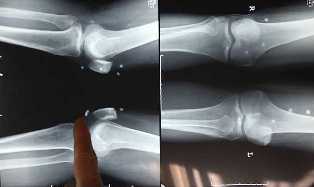

Վիրաբույժ Սինգ Վանայի խոսքով՝ բուժման վայրի մեթոդները քայքայել են նրա ոսկորները, այդ թվում նաեւ գոտկատեղի հոդերը, ուստի տղամարդուն վերականգնողական վիրաբուժության կուրս է սպասվում: